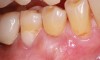

Fig 5. Pre- (Fig 5) and post- (Fig 6) DGV procedure. Note the 7-mm pocket distal to tooth No. 15 before treatment and normal probing depth after treatment. It would have been easier for the restorative dentist to place this crown with increased tooth structure if the tuberosity tissue had been removed previously.

Figure 5

The clinician must determine which of these two harvest techniques should be utilized. Each has its advantages in different situations. For non-wide (buccal-palatal dimension) tuberosities, the DGV technique offers less tissue loss. For wide tuberosities, which are greater than 4 mm in width buccal-lingually and have more CT, the DW technique may be advantageous, as the flap can be approximated and closed with sutures, and this potentially may be more comfortable for the patient. Either technique adequately removes the excess tissue and reduces the pocket. The DGV approach provides a faster tissue harvest and a greater amount of tissue (Figure 5 and Figure 6).